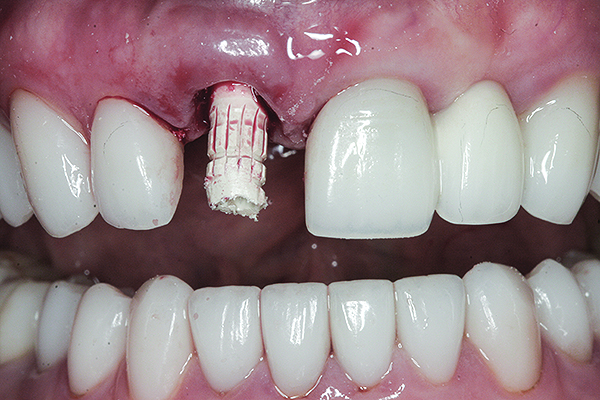

Fig 9. The modified temporary cylinder in position.

Figure 9

Fig 10. The bis-acryl provisional crown was placed on the modified temporary cylinder and allowed to set.

Figure 10